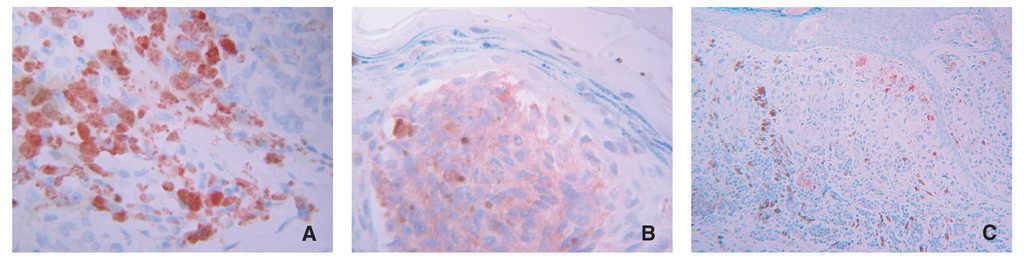

El 23,8 % de las piezas estudiadas (n = 31) mostraron algún tipo de inmunomarcaje para galanina, mientras que este porcentaje fue del 47,7 % de los casos (n = 62) para la α-MSH. Este inmunomarcaje fue citoplasmático en ambos casos, a veces más granular y otras más difuso (fig. 1).

Figura 1.Detalle de inmunomarcajes para (A) galanina, (B) α-MSH y (C) ki-67 en células de melanoma. Obsérvese la diferencia entreel marcaje citoplasmático de los dos primeros y el nuclear del tercero. (A) La galanina muestra en unas células un marcaje granular y en otras más homogéneo.